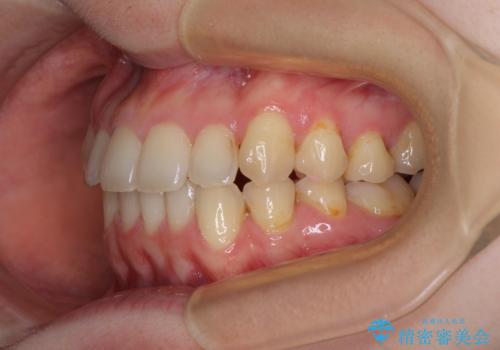

- 八重歯を気にして来院された患者様です。

診査を行ったところ、下顎前歯が1本欠損しており、下顎歯列が上顎よりも小さくなっていることで、上顎にデコボコが生じていました。

口元を見ると抜歯をして突出感を改善するような状態ではなかったため、上顎歯列のデコボコを整えて、歯列全体を後方に移動させることでバランスを取ることとしました。

マウスピース矯正は自己管理が煩わしいとのことで、ワイヤー装置にて矯正治療を行うこととしました。